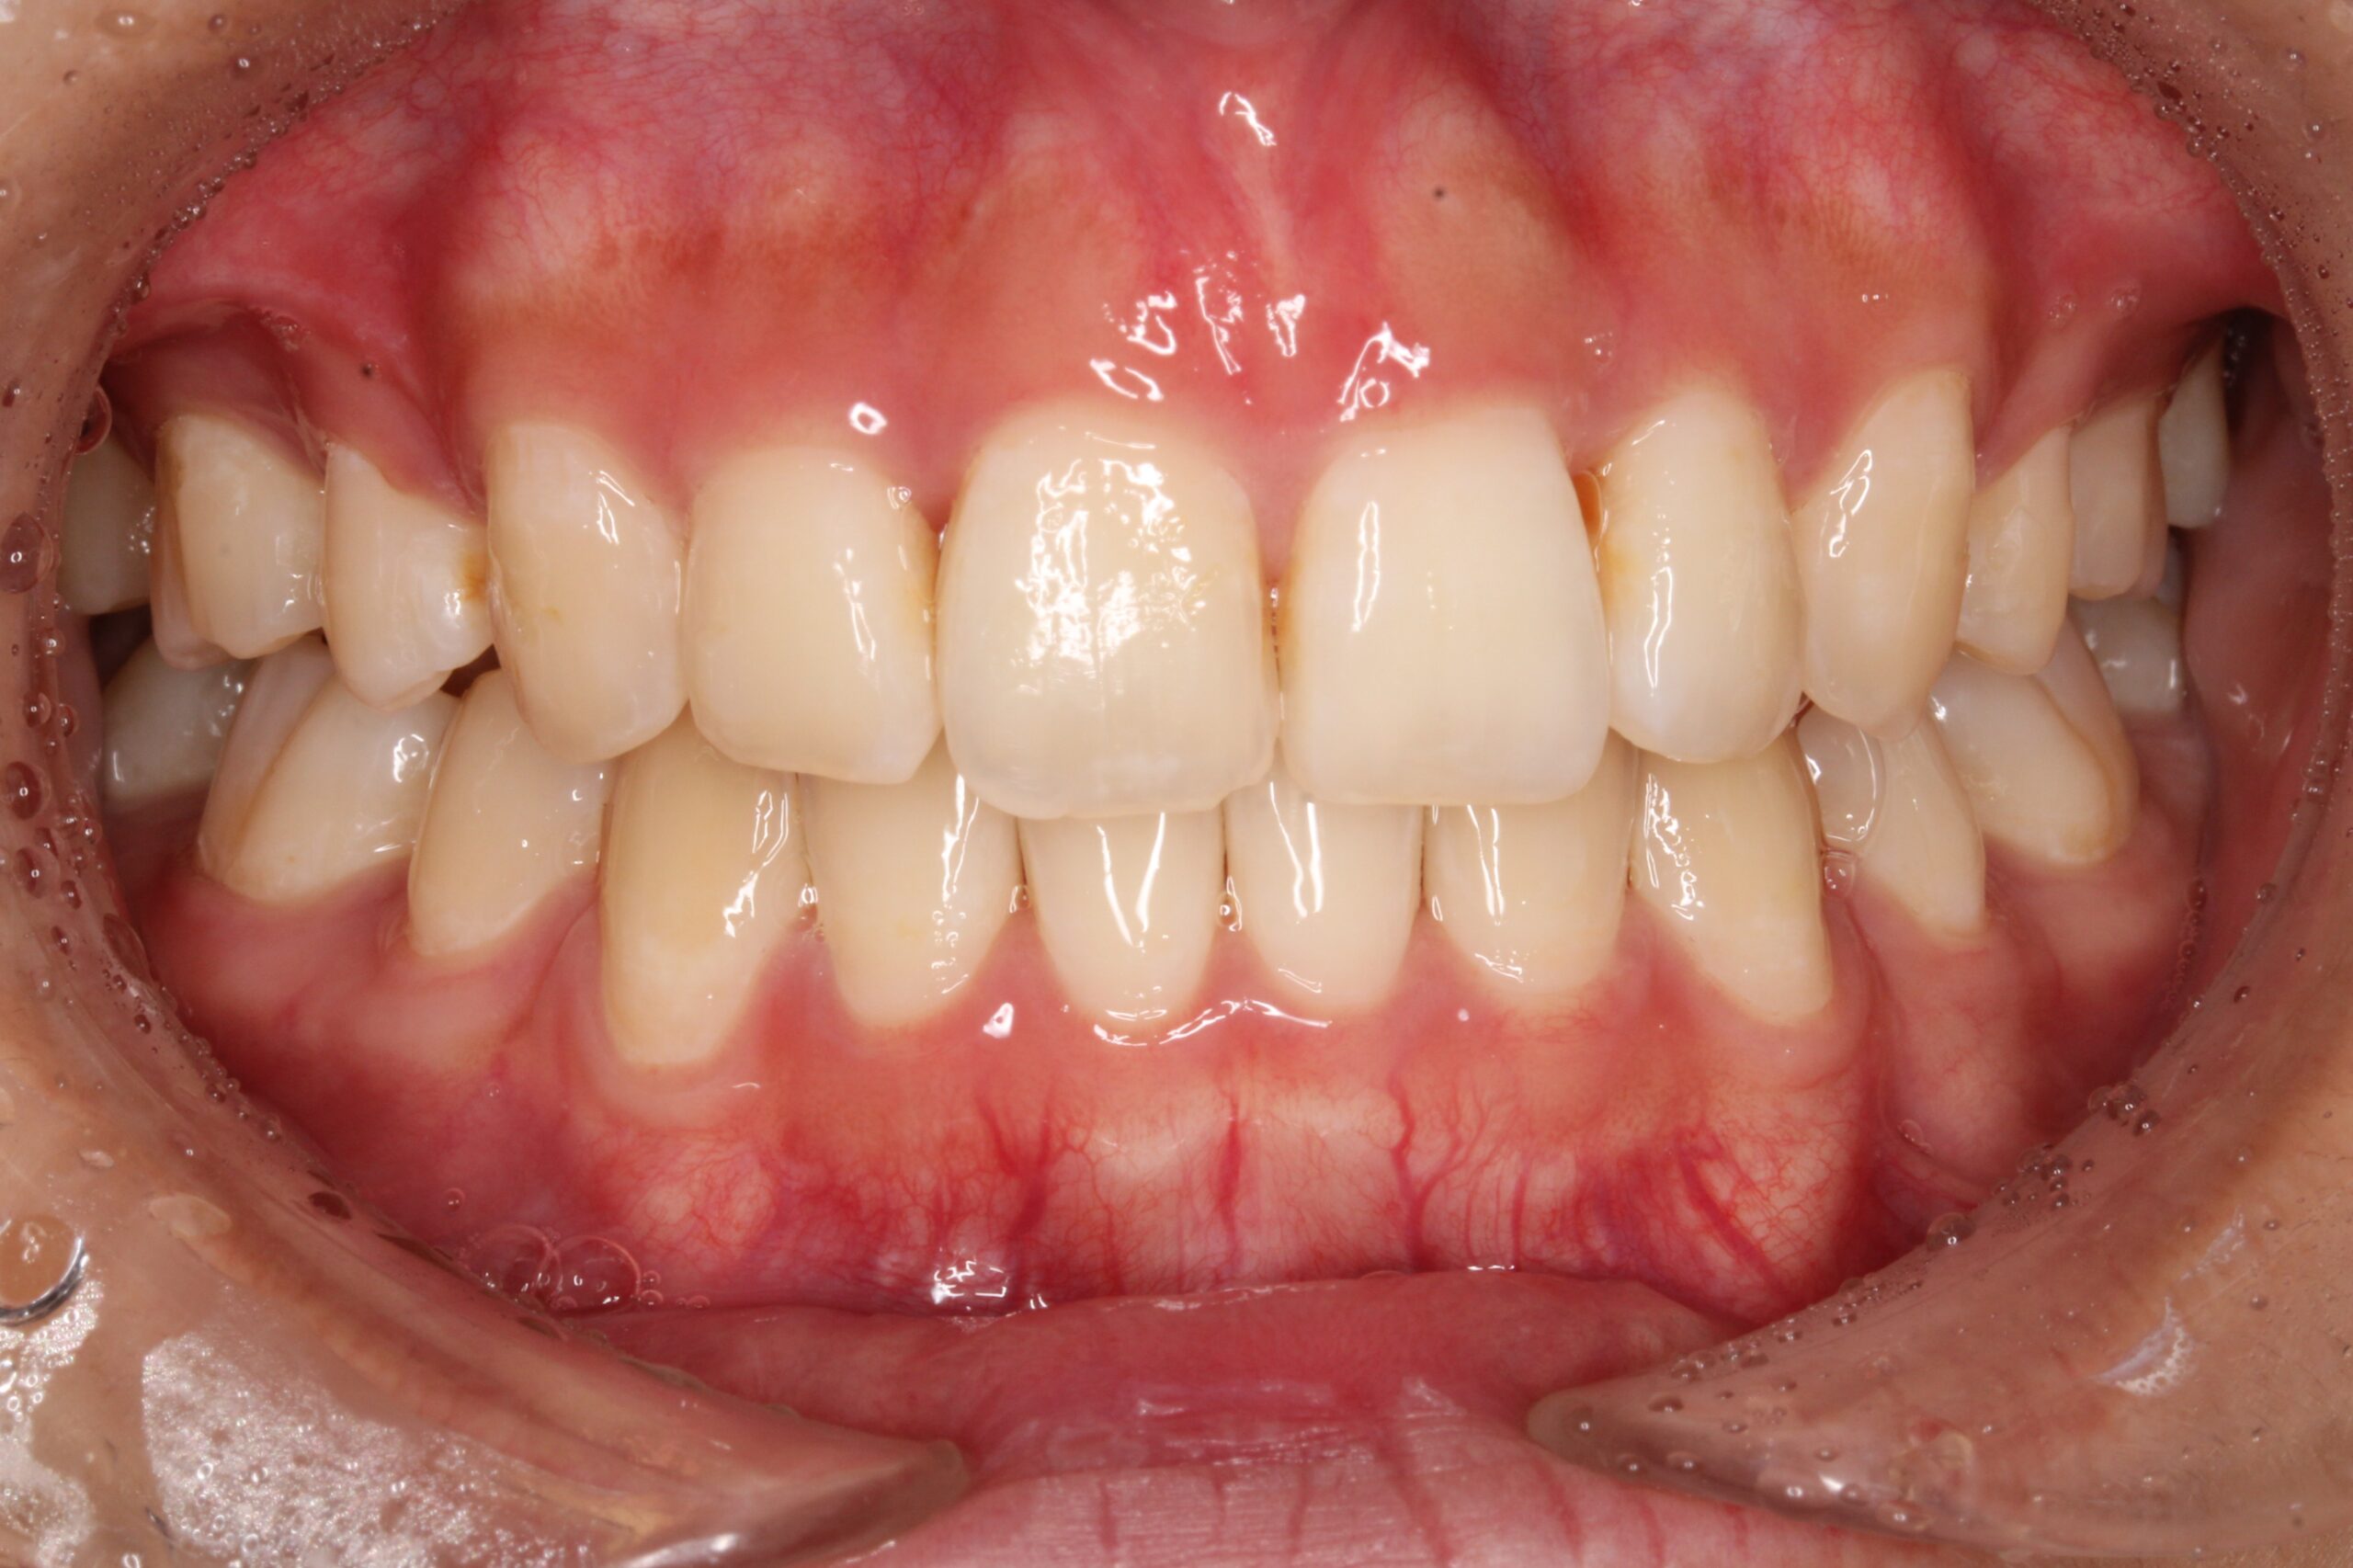

今回ご紹介する患者様は、上下のがたつきを気にされており、矯正検査後叢生Ⅰ級と診断いたしました。

矯正前に、上下小臼歯4本を抜歯いたしました。また、ワイヤー矯正後に、インビザラインで仕上げ矯正を行いました。

矯正術後:正面

| 主訴 | 上下のがたつきが気になる |

| 治療期間 | ・ワイヤー矯正:23カ月 ・インビザライン矯正:15か月 |

| 治療費用 | 1,100,000円(税込) |

| 治療内容 | 患者様は、上下のがたつきを気にされており、矯正検査後叢生Ⅰ級と診断いたしました。矯正前に、上下小臼歯4本を抜歯いたしました。また、ワイヤー矯正後に、インビザラインで仕上げ矯正を行いました。 |